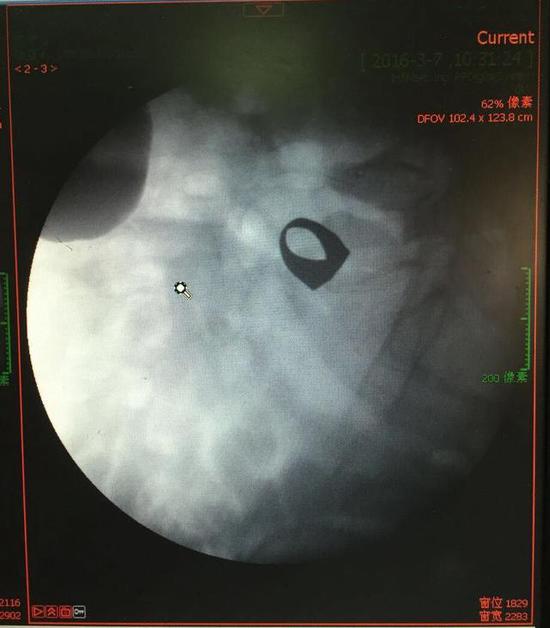

考慮到患者年齡較大,有冠心病,曾經(jīng)中過(guò)風(fēng),高血壓極高危級(jí),遂把老人安排在帶有監(jiān)護(hù)的病房,立即給予吸氧,補(bǔ)液等治療。醫(yī)院立刻開(kāi)啟綠色通道,醫(yī)護(hù)人員專門(mén)陪伴病人做了增強(qiáng)CT,腹部平片,和碘水造影,確定戒指的位置。檢查結(jié)果提示戒指位于右下腹小腸內(nèi),距回盲瓣體表投影約5cm。

3月9日,夏澤鋒教授細(xì)心的給病人做結(jié)腸鏡檢查,找到回盲瓣,調(diào)整結(jié)腸鏡鏡頭,快速的進(jìn)入小腸。結(jié)腸鏡緩緩上行至距離回盲瓣5cm的小腸,沒(méi)有戒指。繼續(xù)上行,至20cm的地方,仍然沒(méi)有找到戒指。

此時(shí)一個(gè)又一個(gè)大大的疑問(wèn)出現(xiàn)在每個(gè)在場(chǎng)的醫(yī)護(hù)人員腦海中,戒指還在小腸里嗎?戒指在哪個(gè)位置呢?夏教授立刻聯(lián)系放射科,拍片子,發(fā)現(xiàn)戒指已經(jīng)移動(dòng)了,從右側(cè)移動(dòng)到了左側(cè)去了。放射科醫(yī)師建議,戒指有可能會(huì)繼續(xù)沿腸道下行,如果過(guò)了回盲瓣,就可以自行排出,免除手術(shù)痛苦。教授們采納了這個(gè)意見(jiàn),立即給予促進(jìn)胃腸道動(dòng)力藥,枸櫞酸莫沙必利片,每日口服三次,另外配合灌腸治療,促進(jìn)腸道蠕動(dòng),利于戒指排出。